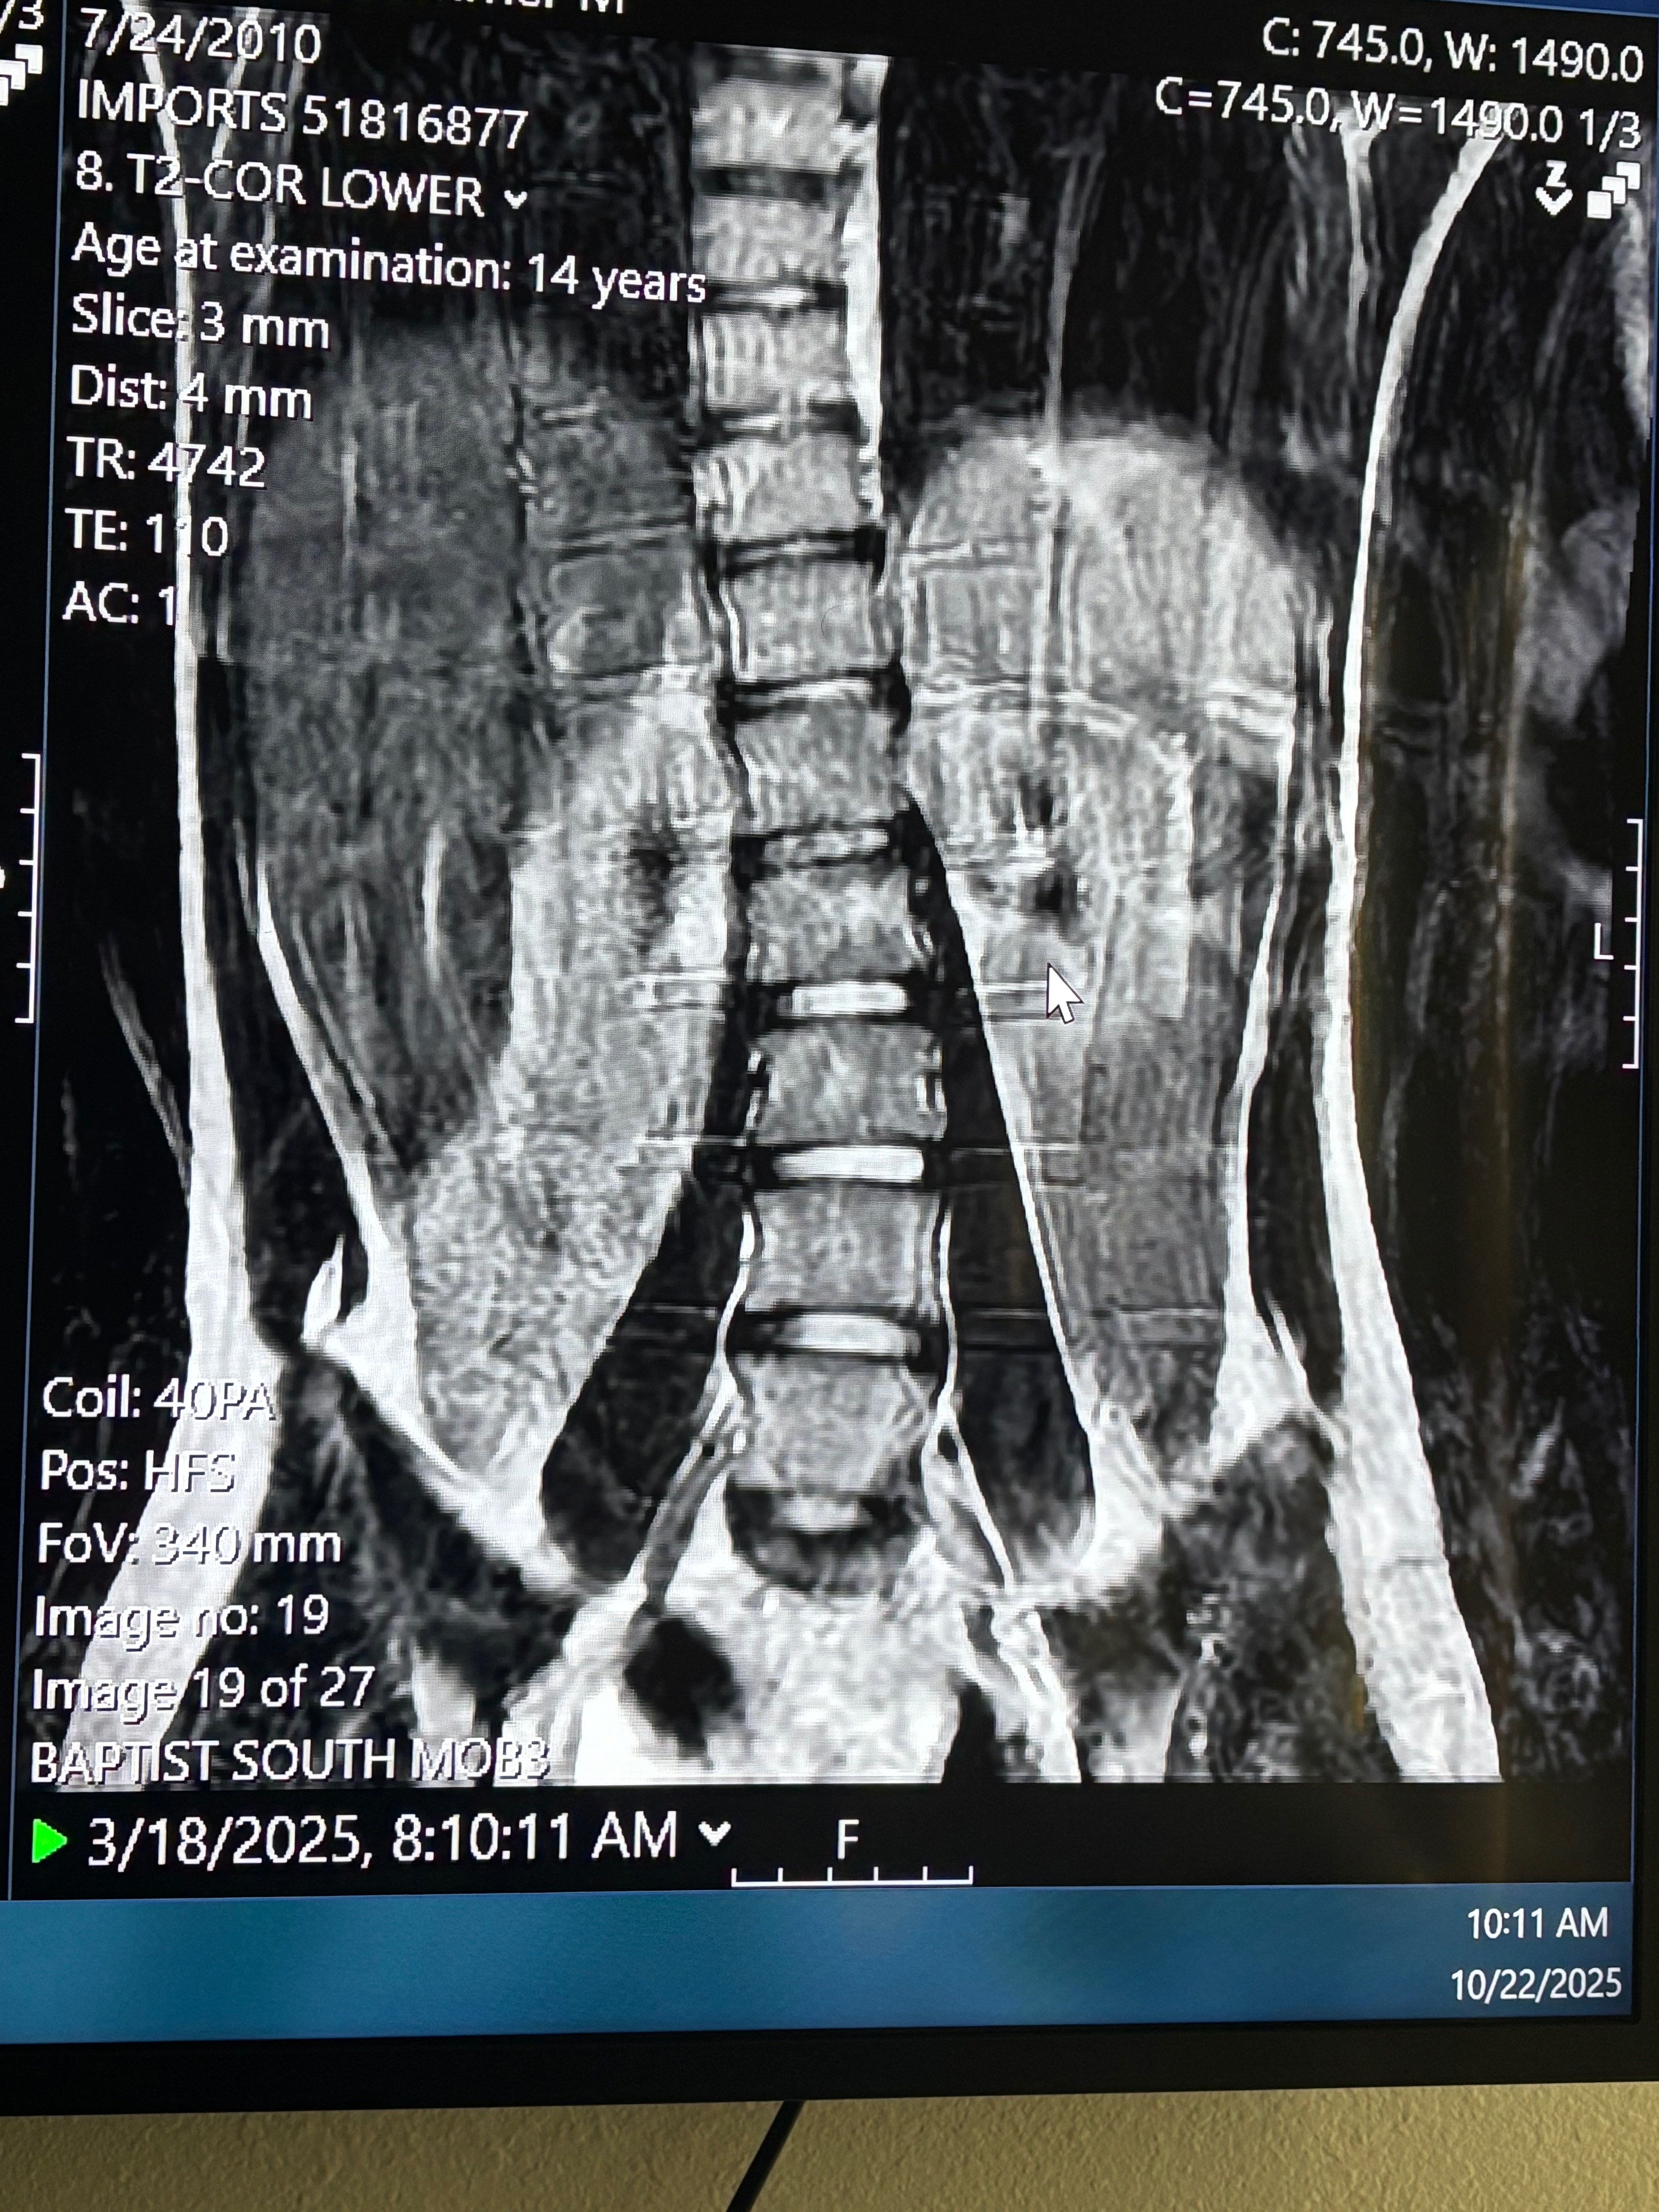

I'm raising money as a 15-year-old teen who has been suffering with chronic back pain . The pain has affected my daily life, can’t even sit still in school, go to the nurse crying. I’ve tried everything in the books, physical therapy, ibuprofen, Tylenol, heat, ice, chiropractors, braces, you name it. After all of that you lose hope I lost hope in a diagnosis and getting seen and heard, it takes a toll on anyone but especially a 15 year old girl. But, after 3 years of struggling, putting money to things that don’t work, multiple doctors with no answer, there was finally ONE who heard my cries and struggles and finally found the answer to my pain and solution but, struggling to pay.

Since we've FINALLY got our answers summer needs surgery and we need your help!